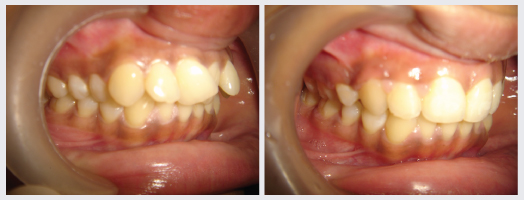

Orthodontics, popularly known as Braces treatment is a speciality of Dentistry that deals with the correction of Malocclusion or Malalignment. It is used to correct crowded teeth, protruded teeth, dental spaces, Jaw Deformities, improper bites and crooked smiles. At DENTAL QUE Orthodontic treatment is done for all age groups and there are types of braces available to suit everyones needs.